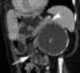

Calcified renal cyst

A renal cyst is a fluid collection in or on the kidney. There are several types based on the Bosniak classification. [Source: Wikipedia ]